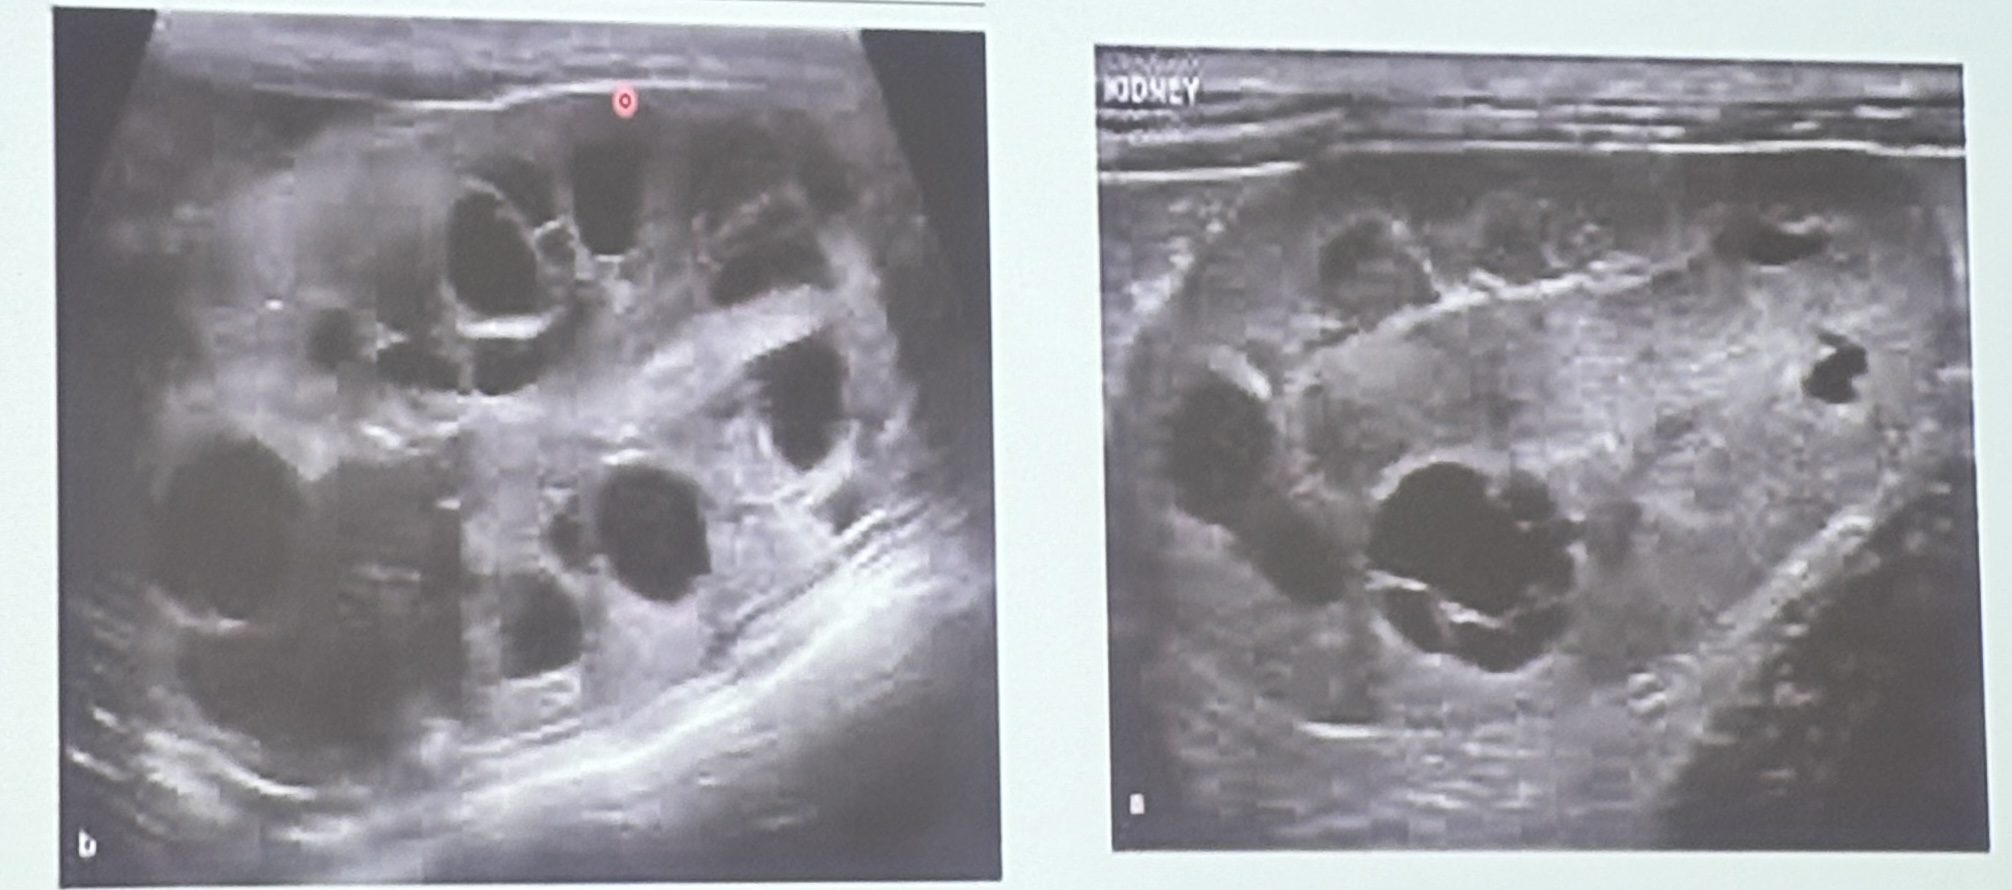

These are long axis scans for the left & right kidneys of a 7yo DSH with a history of azotemia. What are the ultrasonographic findings?

Polycystic kidneys